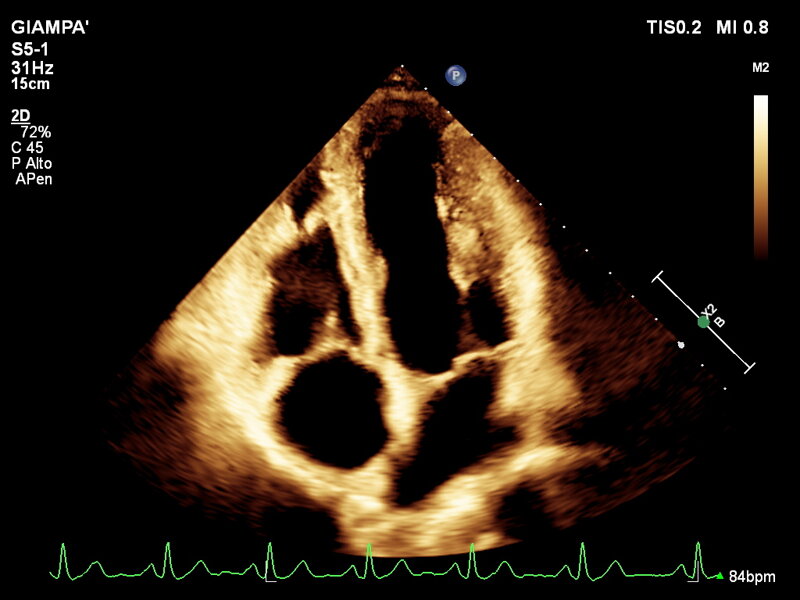

L’ecocardiografia è una metodica con cui si studiano il cuore e il flusso del sangue attraverso le valvole per mezzo degli ultrasuoni. permette di ottenere informazioni sulla contrattilità del cuore, sulla morfologia delle sue valvole e sul flusso del sangue nelle sue cavità, sia a riposo che dopo l’esercizio fisico